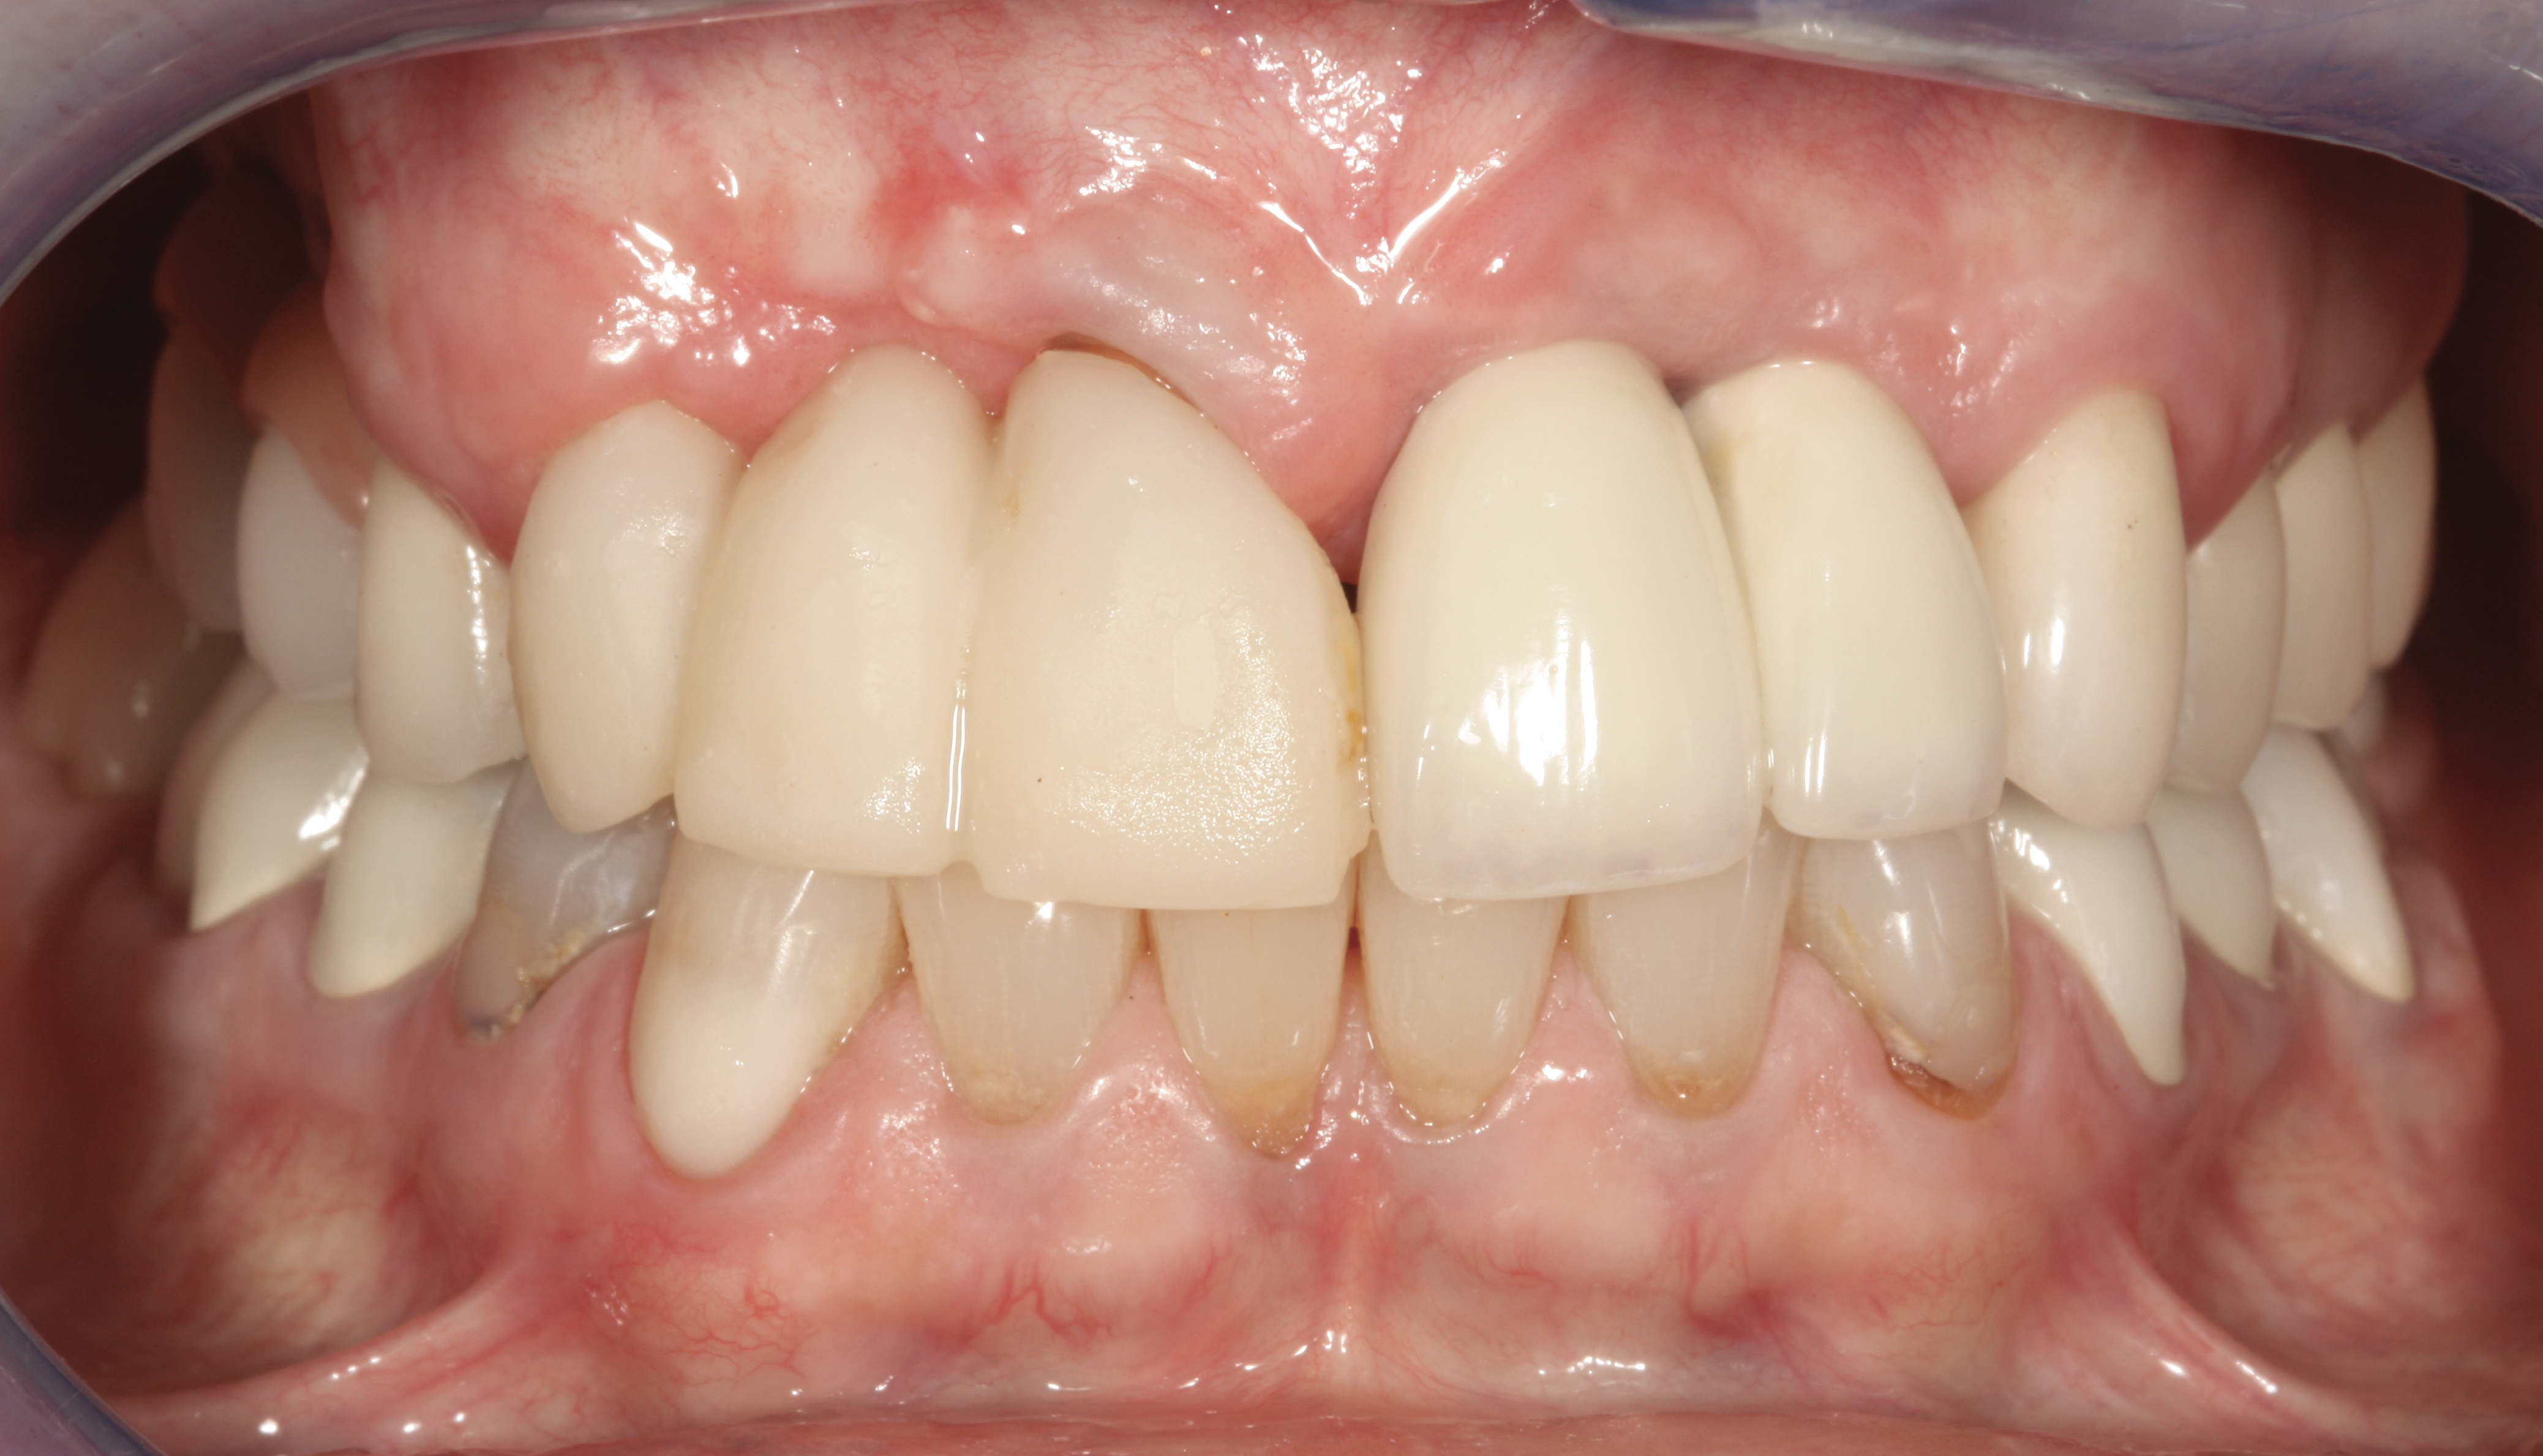

Fig 45. The definitive crown tooth No. 26 seated in place and provisionally cemented. The recession defect was eliminated with the removal and replacement of a new implant in the proper position.

Figure 45

Fig 46. The post-treatment radiograph showing a healthy stable implant and restoration.

Figure 46